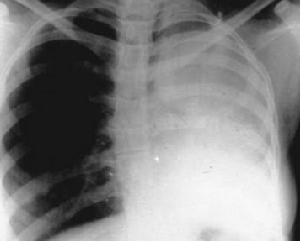

肺爆震傷的臨床表現因傷情輕重不同而有所差異。輕者僅有短暫的胸痛、胸悶或憋氣感。稍重者傷後1~3天內出現咳嗽、咯血或血絲痰,少數有呼吸困難,聽診可聞及變化不定的散在性濕羅音或捻發音。嚴重者可出現明顯的呼吸困難、發紺、血性泡沫痰等,常伴休克。查體除肺內羅音外可有肺實變體徵和血氣胸體徵。此外,常伴有其他臟器損傷的表現。X線檢查肺內可見肺紋理增粗、斑片狀陰影、透光度減低、以至大片狀密影,亦可有肺不張和血氣胸的表現。血氣檢查可出現輕重不等的異常結果。根據爆炸傷史、臨床表現和X線檢查,肺爆震傷容易確診,但應注意其外輕內重、迅速發展和常有合併傷的特點,慎勿誤診和漏診。

X線檢查肺內可見肺紋理增粗、斑片狀陰影、透光度減低、以至大片狀密影,亦可有肺不張和血氣胸的表現。